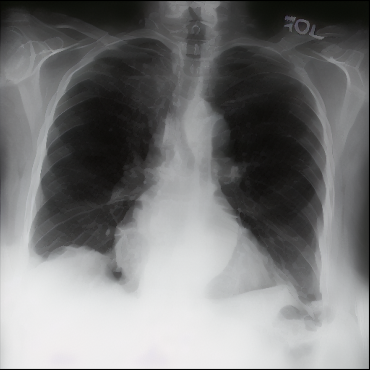

Figure 2: Fusion process applied to an image from the tail class Tortuous Aorta (a.1) and one of its neighbor images from the head class Atelectasis (b.1). (a.2) and (b.2) are channelwise Maximum Intensity Projections of the sparse vectors obtained from (a.1) and (b.1) respectively. In (a.3) and (b.3), we use EigenCAM to find attention maps for each sparse vector and define binary masks (yellow is one and dark purple is zero) using τh=τl=0,4formulae-sequencesubscript𝜏subscript𝜏𝑙04\tau_{h}=\tau_{l}=0,4 as thresholds. We combine the masked sparse vectors into (c) and decode the vector into a fused image (d). Finally, we apply five inference steps in (e) to obtain a less noisy image.

The method was tested by generating tail classes of a sampled version of MIMIC-CXR-LT 2023 [16, 13], a multilabel multiclass long-tailed dataset of chest X-rays. Our reduced sample version has only five head classes and five tail classes.